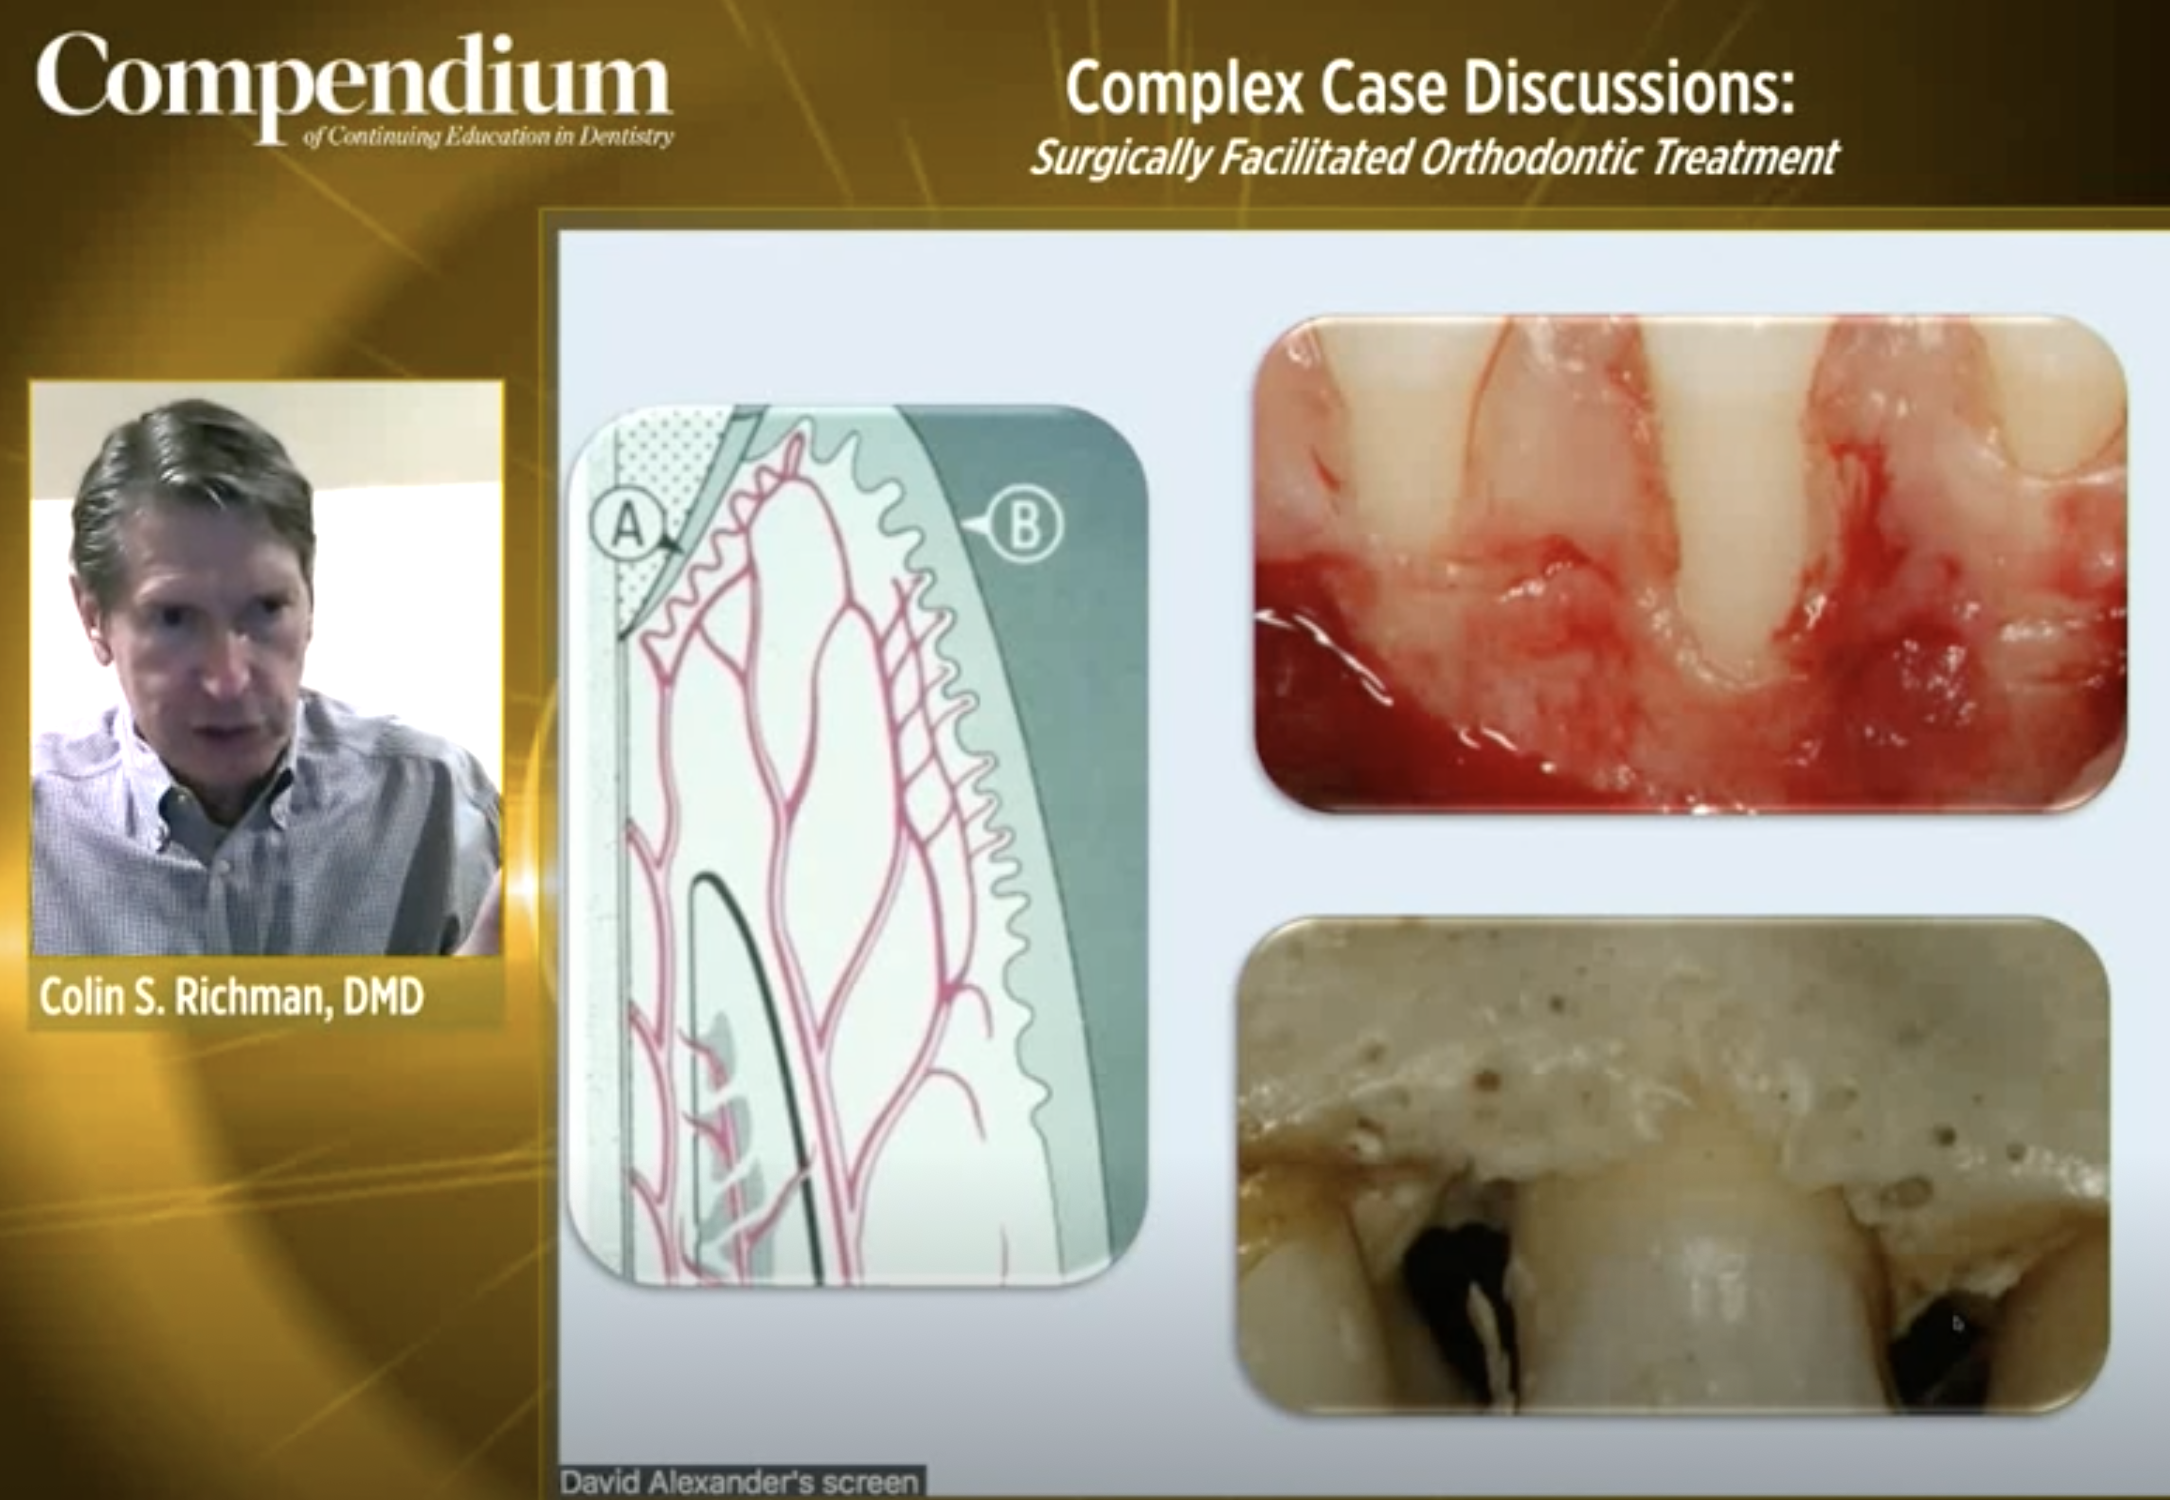

ON-DEMAND CE Webinar Complex Case Discussions: Surgically Facilitated Orthodontic Treatment Irina Dragan, DDS, MS; David C. Alexander, BDS, MSc, DDPH; J. Kobi Stern, DMD, MSc; Stuart Beauchamp, DMD; Marielle Beauchamp, DMD; and Colin S. Richman, DMD Credits: 1 SI Cost: Free Commercial Supporter: Align Technology, Inc., and Invisalign® |